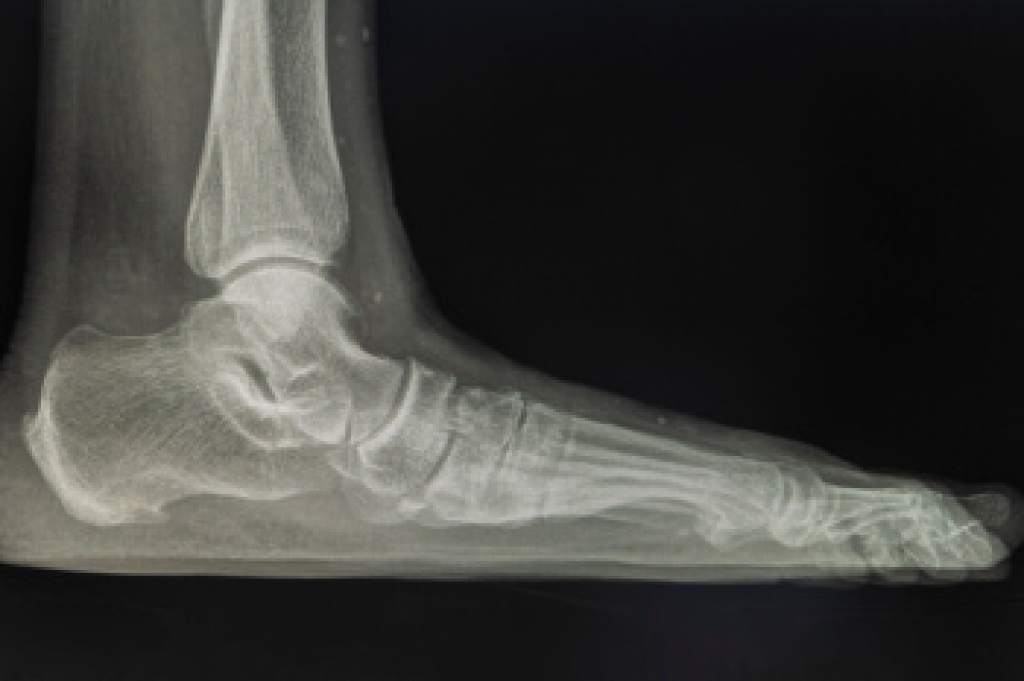

In order to diagnose your bunion, your podiatrist may ask about your medical history, symptoms, and general health. Your doctor might also order an x-ray to take a closer look at your feet. Nonsurgical treatment options include orthotics, padding, icing, changes in footwear, and medication. If nonsurgical treatments don’t alleviate your bunion pain, surgery may be necessary.